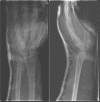

Isolated ulnopalmar dislocation of the fifth carpometacarpal joint

Dislocations of the carpometacarpal (CMC) joints are uncommon and are frequently missed on standard radiographs of the hand. Dislocations could be dorsal or palmar; dorsal dislocations are seen more frequently. Palmar dislocations can be either ulnopalmar or radiopalmar. Stable CMC dislocations could be successfully treated conservatively, while unstable dislocations are mostly treated operatively. The purpose of this report is to present a patient with an isolated ulnopalmar dislocation of the fifth CMC joint, satisfactorily treated with closed reduction and casting.